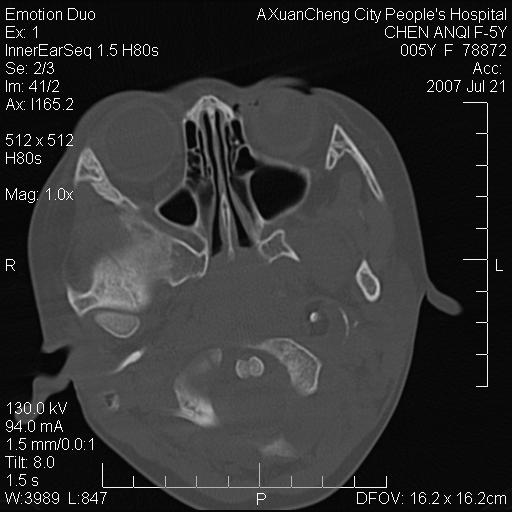

标题: PED0273:5岁,左耳流脓痛疼一周,颅底骨质破坏 [打印本页]

标题: PED0273:5岁,左耳流脓痛疼一周,颅底骨质破坏

患儿5岁,左耳流脓痛疼一周,左外耳道肉芽组织填塞 软组织窗显示病灶内结节状低密度影为气体密度

考虑中耳乳突炎并胆脂瘤形成可能。

左侧中耳炎并胆脂瘤,左颞骨岩部骨质破坏并颅内感染积气。

考虑化脓性中耳乳突炎伴胆脂肪瘤形成并左颞叶感染,不除外合并嗜酸性肉芽肿.